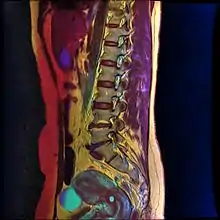

Nabothian cysts are also incidentally found during MRI imaging. During the healing process of chronic cervicitis, squamous epithelium of ectocervix proliferates and enter the cervical canal (endocervix), covering and obstructing the columnar epithelium of endocervical glands. Thus, retention of mucus in the endocervical glands causes cyst formation. The size of the cyst may vary from a few millimetres to 4 cm in diameter.[3]

If a cyst has an unusual appearance, a colposcopy will be performed to rule out other diagnoses.[4] If the blood vessels are short, comma-like or corkscrew-shaped and bleed on contact, then the cyst may be a very rare mucin-producing carcinoma of the cervix.[4] Magnetic resonance imaging is used to distinguish cancer from the typical nabothian cyst.[4]

T1-weighted MRI imaging would show intermediate to high intensity while T2-weighted imaging would show high signal intensity. Findings of solid components separating multiple cysts would be suggestive of adenoma malignum (a form of cervical cancer).[3]